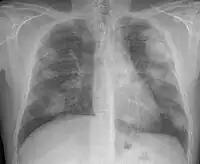

There are three key elements to the diagnosis of silicosis. First, the patient history should reveal exposure to sufficient silica dust to cause this illness. Second, chest imaging (usually chest x-ray) that reveals findings consistent with silicosis. Third, there are no underlying illnesses that are more likely to be causing the abnormalities. Physical examination is usually unremarkable unless there is complicated disease. The examination findings are not specific for silicosis.[19]

For uncomplicated silicosis, chest x-ray will confirm the presence of small (< 10 mm) nodules in the lungs, especially in the upper lung zones. Using the ILO classification system, these are of profusion 1/0 or greater and shape/size "p", "q", or "r". Lung zone involvement and profusion increases with disease progression. In advanced cases of silicosis, large opacity (> 1 cm) occurs from coalescence of small opacities, particularly in the upper lung zones.

With retraction of the lung tissue, there is compensatory emphysema. Enlargement of the hilum is common with chronic and accelerated silicosis. In about 5–10% of cases, the nodes will calcify circumferentially, producing so-called "eggshell" calcification. This finding is not pathognomonic (diagnostic) of silicosis. In some cases, the pulmonary nodules may also become calcified.

Chest X-ray showing uncomplicated silicosis